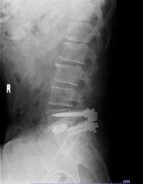

治療について

受診された際には問診、診察を行い、画像検査(レントゲン、MRI、CT)や採血検査を行い、診断を付け、治療方針を説明します。 上記のような保存治療を行っても取れない痛みや、手の使いにくさや歩行困難、排尿排便障害などが出現し症状が進行性の場合は手術加療が必要となります。

手術・検査

なるべく低侵襲で体の負担が少ない手術を行います。低侵襲な脊椎手術には、手術による傷が小さい、筋肉の損傷が少ない、出血量が少ない、時間が短い、術後の痛みが少ない、早期リハビリテーションが可能、早期退院が可能(10日程度)、早期社会復帰が可能、など多くの利点が挙げられます。

検査

当院では、術前の診断精度を高める目的で、神経根ブロック(左)やCTミエログラフィー(右)検査を行っています。検査後は、経過を確認する目的で1泊入院となりますが、翌日には退院が可能です。